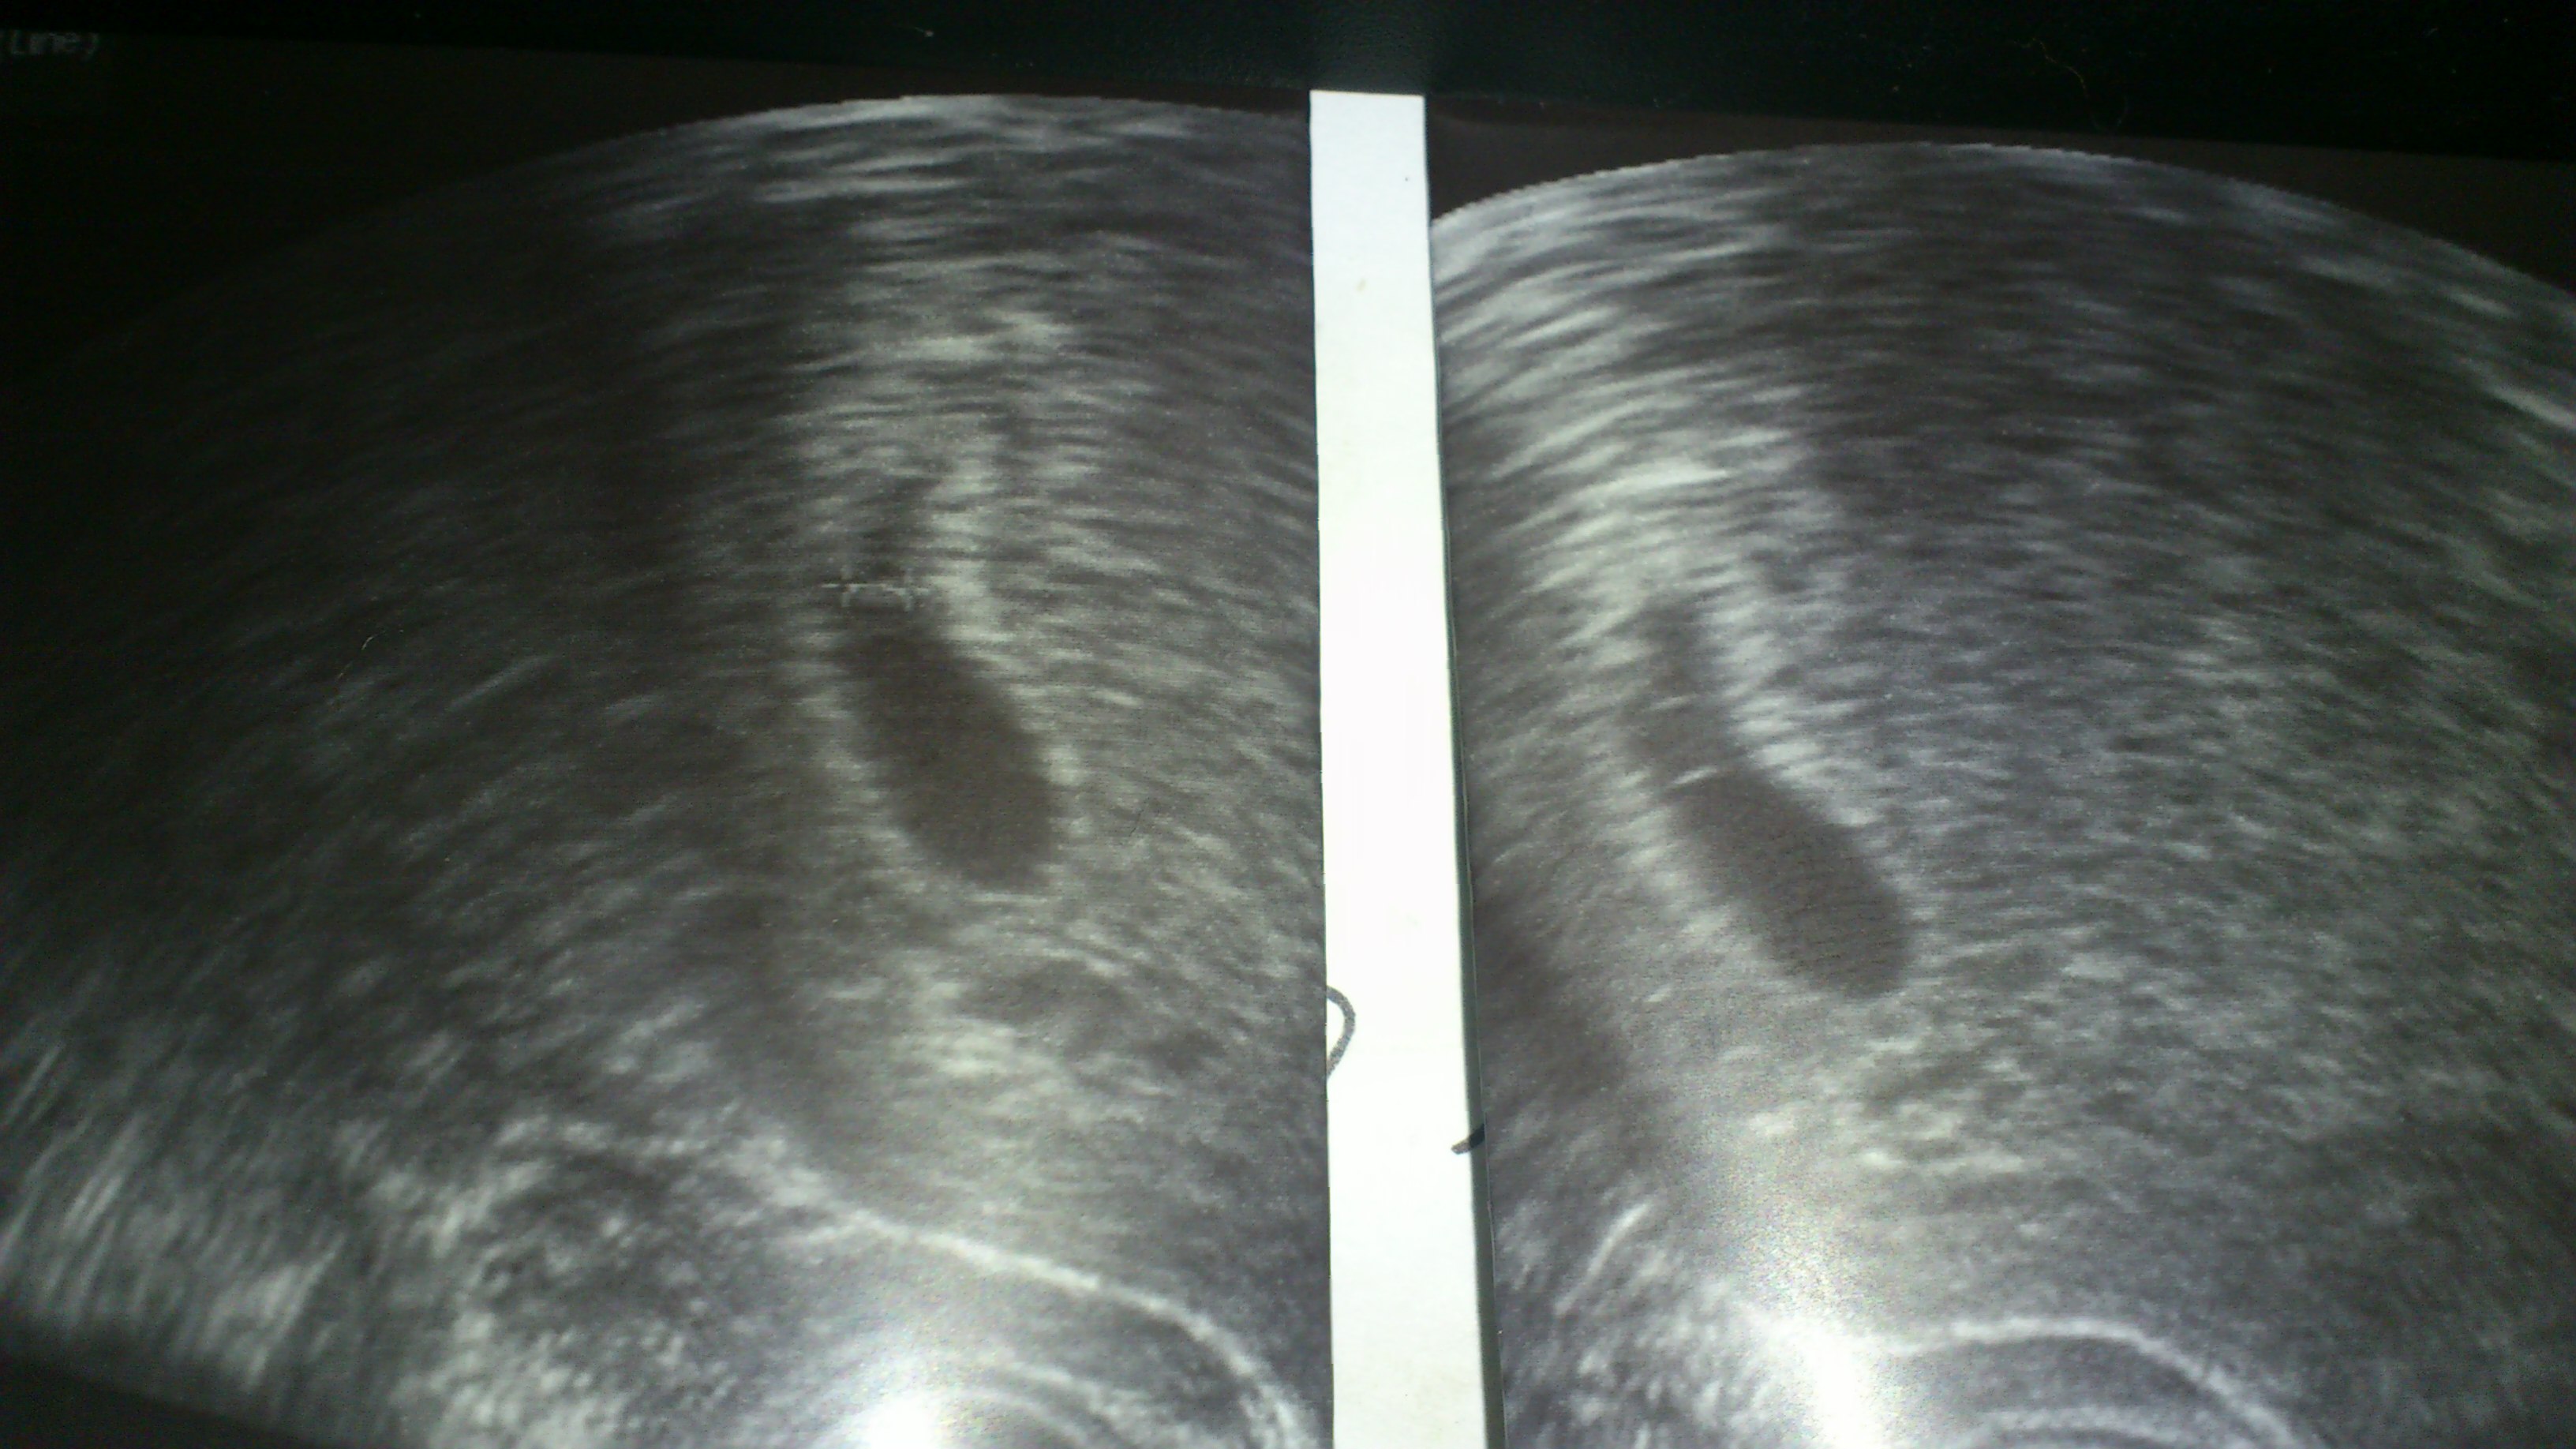

@ Me : so, aber nun zu mir ..... ich hab es nichtmehr ausgehalten diese ungewissheit .... hab in meiner KiWu angerufen und auch gleich einen Termin für heute bekommen war zwar nicht meine Ärztin aber auch eine sehr nette .... hat sich schön zeit genommen für den US und was soll ich sagen :dance: .... seht selbst sie hat eine Fruchthöhle mit Dottersack rechtes Bild und den Embryo ca. 3 mm linkes Bild (ist markiert ) gefunden .... wenn ich die Luft angehalten habe konnte man so gar ganz leicht und schwach das Herzchen sehen :juhu: :juhu: :juhu: man bin ich jetzt beruhigt .....

DSC_0047.JPG

30.11.12 - US Herzchen schlägt - Krümel ist 4,1 mm groß